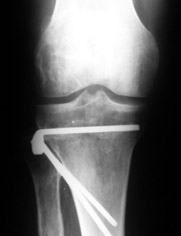

a> Совершщенно беспредметный спор. Лучше бы спорили как менее травматично

Как уже писал, вчера сделал одну ногу (может, свой плюс будет что не обе- вдвое меньше травма, сразу на костыли встанет, оперированную ножку немного разомнет, тут и вторую заделаем).

Операция была интересной, много полезного опыта приобрел.

Снимки в приложении - фас сравнительный с неоперированной ногой. Жду критики.

Впрос про остеотомию большеберцовой непраздный. Эта получилась при надломе несколько более наклонно, чем я делал (сейчас проблема,

как на второй ноге сделать так же). Вот этот высоящий "зуб" центрального отломка не заменит ли в плане косметики то, что получается при медиализации дистального?